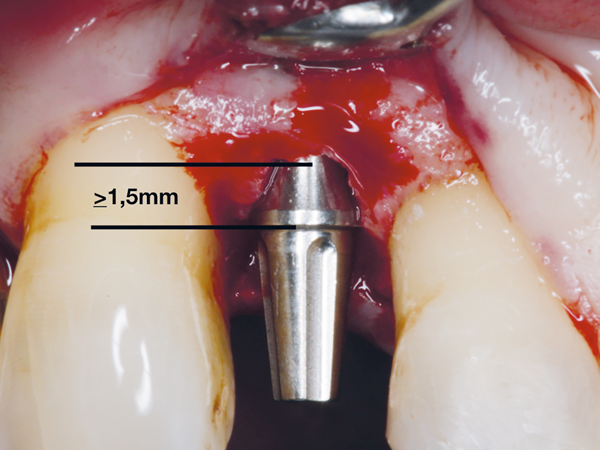

Outros fatores de risco, como fumo, altura do pilar protético em relação à crista óssea e diâmetro do implante, também foram avaliados. Dentre estes, pilares com cinta de 0,8 mm (Figura 3) foram mais suscetíveis à perda óssea quando comparados aos pilares de cinta maior do que 1,5 mm (Figura 4).

Figura 4 – A altura ideal da cinta do pilar deve ser maior ou igual a 1,5 mm.